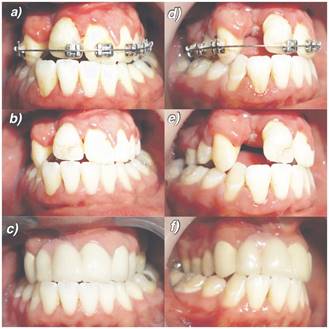

Paciente D.C.R de 16 años de edad, sexo masculino, acude a la Unidad de Malformaciones Craneofaciales de la Facultad de Odontología de la Universidad de Chile para tratamiento de Ortodoncia, con fístula buconasal de 2,1 cm de diámetro en sentido transversal en su diámetro mayor, como secuela de fisura unilateral derecha de labio, paladar y velo. El paciente presenta una clase II esqueletal con falta de desarrollo del tercio medio facial. En sentido sagital presenta una distoclusión molar bilateral y un resalte negativo de -0.5 mm, en sentido transversal una mordida cruzada bilateral y en sentido vertical un escalón disminuido, con un valor de 0 mm.

Se realiza interconsulta a Cirugía Plástica para la evaluación del cierre de la fístula y coordinar el inicio del tratamiento de ortodoncia. Este último se planifica en base a la realización de una expansión (mínima) del maxilar para la mejora en sentido transversal de la anomalía, de acuerdo a lo conversado y coordinado con el cirujano, para posteriormente alinear y nivelar las arcadas mediante tratamiento correctivo.

Se decide coordinar una nueva cirugía de paladar para el cierre de la fístula mediante injerto de lengua (cicatrización por 1° intención) y el desligue a las 3 semanas (cicatrización por 2° intención). A los 6 meses de realizada esta cirugía se decidió realizar injerto óseo alveolar derecho para lo cual se prepara ortodóncicamente la posición de dientes adyacentes.

Una vez realizado el injerto, se realiza el retiro de aparatología fija de ortodoncia y la coordinación para el inicio de la rehabilitación estética mediante prótesis fija plural, la cual utiliza como pilares las piezas 1.3, 2.1 y 2.2 para rehabilitar las piezas 1.2 y 1.1. Esto busca, además, mejorar la anatomía dentaria de los incisivos centrales superiores derecho e izquierdo y a su vez, mejorar la estética de todo el sector anterior.

Luego del procedimiento quirúrgico y tras realizar los controles postoperatorios, se ha observado una mantención y estabilidad del injerto en la zona de la fístula desde el momento de la cirugía a la fecha. Además, se ha producido una notable mejoría en el habla (al mejorar la IVF 9 a una IVF 2) y alimentación del paciente, influyendo positivamente en sus relaciones interpersonales y autoestima.